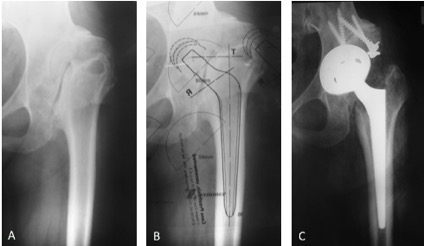

Introducción: El objetivo de este estudio es analizar nuestros resultados clínico-radiológicos con el uso de copas de tantalio trabecular para la reconstrucción de acetábulos complejos, tanto en cirugías primarias como en revisiones, y com- pararlos con series similares de otros autores. Materiales y Métodos: Se llevó a cabo una revisión retrospectiva de una serie de 42 cirugías (29 revisiones y 13 artro- plastias primarias) en 40 pacientes, entre marzo de 2010 y marzo de 2016. La serie incluyó a 20 mujeres y 20 hombres, con una edad promedio de 60 años (rango 27-93). El seguimiento promedio fue de 37 meses (rango 12-84). Todos los pacientes fueron tratados con el mismo tipo de metal trabecular. Resultados: Al promedio de seguimiento mencionado la supervivencia del componente acetabular fue del 97,6%. Un paciente fue tratado con artroplastia de resección debido a una infección persistente. La tasa de complicaciones totales fue del 12% y el promedio del Harris Hip Score posoperatorio fue de 81,54 (rango 63,25-92,75). Conclusiones: Aunque se necesita un seguimiento más prolongado, el uso de copas de metal trabecular logra resultados prometedores para el tratamiento de acetábulos complejos.